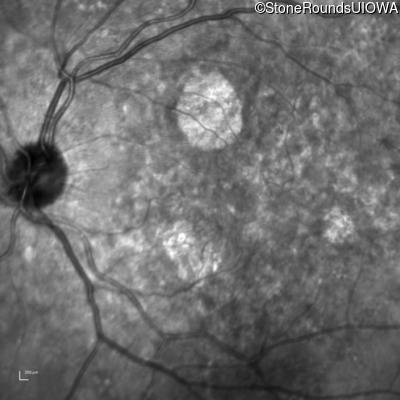

Infrared Fundus Photograph - Right - 20/20

Exemplar